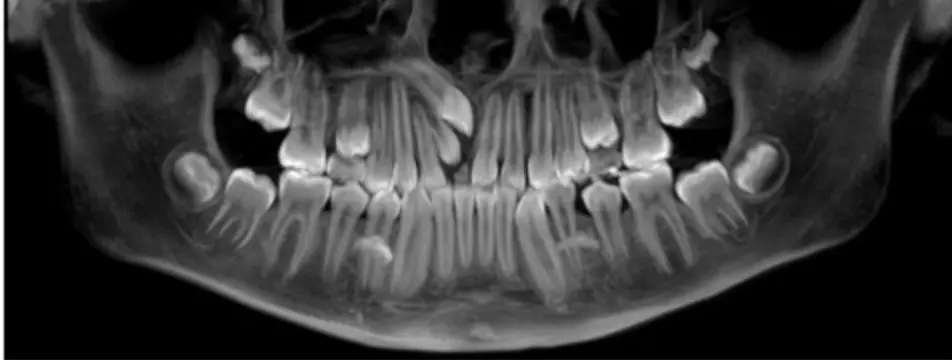

Panoral

November 24, 2025 How good are radiographs constructed from low dose CBCT? Read more